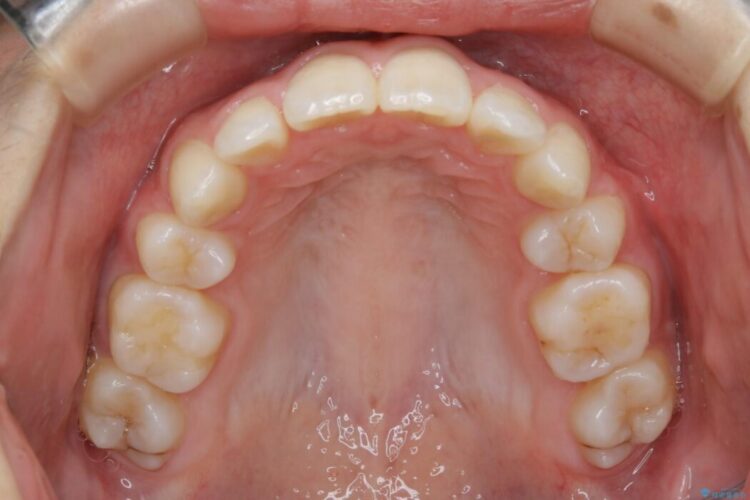

検査したところ歯に対して骨が上顎・下顎共に小さいことがわかりました。

それによりスペースが少なく歯列がガタついたり前方傾斜する生え方となっていました。

本症例の患者様は顎の骨が小さく歯をきれいに並べるための隙間がないため、歯が重なったり傾斜してしまっていました。